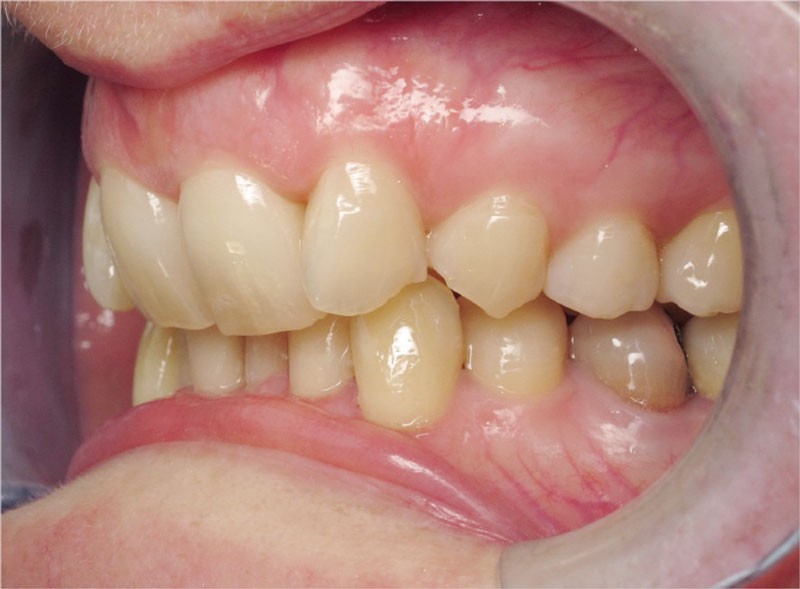

Cas n° 2

Nous lui avons donc proposé un traitement d’alignement avec maintien des 14 et 24 en position de 13 et 23 et optimisation du torque pour favoriser un développement des arcades et chercher à améliorer le sourire et le soutien labial.

La patiente donne son accord pour un appareillage Damon Insignia métal qui permet une individualisation complète des brackets dans les 3 sens de l’espace.